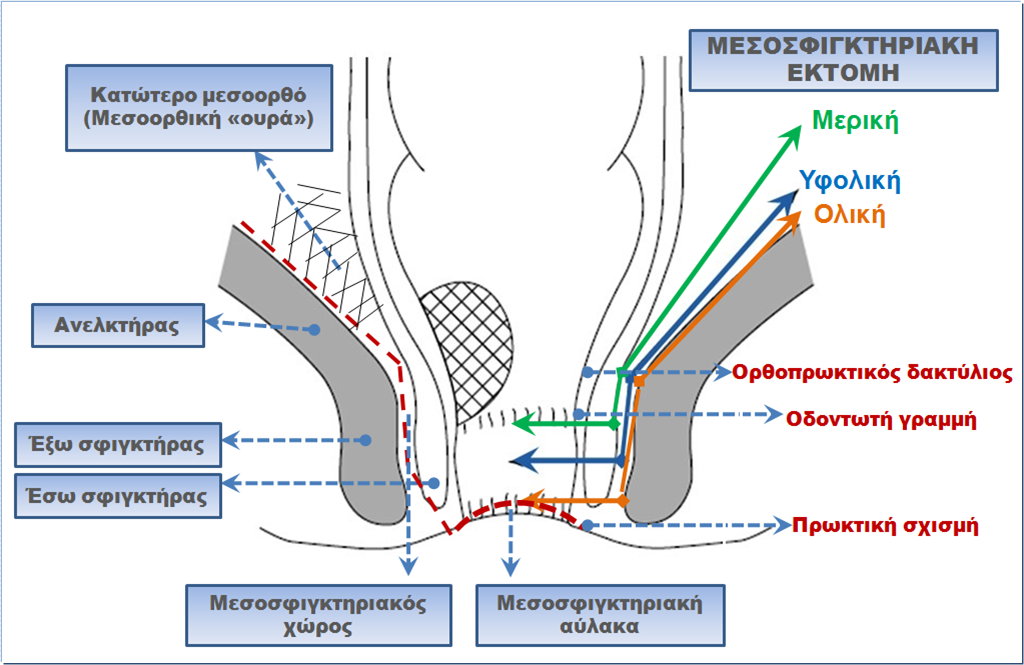

Το πέρας του ορθού αντιστοιχεί και με το κατώτερο σημείο στο οποίο εκτείνεται το μεσοορθικό λίπος, το οποίο είναι γνωστό και ως «μεσοορθική ουρά» οπισθίως, ενώ καθίσταται σχεδόν ανύπαρκτο προσθίως του κατώτερου ορθού. Ο ορθοπρωκτικός δακτύλιος, δηλαδή η πρόσφυση του ανελκτήρα μυός στο κατώτερο ορθό, οριοθετεί το σημείο μετάπτωσης του ορθού στον πρωκτικό αυλό. Ο ανελκτήρας συνέχεται ανατομικά με τον έξω σφιγκτήρα, ο οποίος περιβάλει τον πρωκτικό αυλό. Η συνέχεια του κυκλοτερούς μυϊκού χιτώνα του ορθού αποτελεί τον έσω σφιγκτήρα του πρωκτού. Ο χώρος ανάμεσα στον έσω και στον έξω σφιγκτήρα αποτελεί τη φυσική συνέχεια του περι-μεσοορθικού διαστήματος, οπότε η περιμετρική παρασκευή στο ανάγγειο πλάνο της ολικής μεσοορθικής εκτομής μπορεί να επεκταθεί περιφερικά για όγκους του κατώτερου ορθού που εμφανίζουν επέκταση στο πρωκτικό κανάλι. Αυτή η τακτική εμφανώς απαιτεί αφαίρεση άλλοτε άλλου μήκους του έσω σφιγκτήρα. Το τμήμα του σφιγκτήρα που θα αφαιρεθεί θα καθορισθεί από το απώτερο όριο του πρωκτικού αυλού, το οποίο θα αποτελέσει και το περιφερικό όριο εκτομής προκειμένου να επιτευχθεί το επιθυμητό ογκολογικά περιφερικό όριο εκτομής. Το τελευταίο βιβλιογραφικά υποστηρίζεται ότι πρέπει να είναι από μικροσκοπικά ελεύθερο διηθήσεως έως και 1 εκατοστό.

Στη βάση (α) των ανωτέρω ανατομικών δεδομένων, (β) της απόδειξης ότι η περιφερική εξάπλωση του καρκίνου του κατώτερου ορθού είναι μάλλον σπάνιο ιστολογικό φαινόμενο (γεγονός που έχει ελαχιστοποιήσει το μήκος του ογκολογικά αναγκαίου περιφερικού ορίου) και (γ) του γεγονότος ότι το σύμπλεγμα των γραμμωτών μυών ανελκτήρα και έξω σφιγκτήρα είναι διαφορετικό όργανο από το σύμπλεγμα του έσω σφιγκτήρα-πρωκτού που αποτελούν φυσική ανατομική συνέχεια του κατώτερου ορθού προς τα κάτω (οπότε η αφαίρεση του δεν είναι ογκολογικά αναγκαία στα πλαίσια της κοιλιοπερινεϊκής εκτομής, εκτός και αν διηθείται κατά συνέχεια ιστού - το τελευταίο το αποκλείει η σταδιοποιητική αξιολόγηση με τη μαγνητική τομογραφία), αναπτύχθηκε η μεσοσφιγκτηριακή εκτομή για την αντιμετώπιση επιλεγμένων καρκίνων του κατώτερου ορθού.

Η μεσοσφιγκτηριακή εκτομή, που περιγράφηκε για πρώτη φορά από τους Schiessel και συν το 1994, «εκμεταλλεύεται» το ανάγγειο πλάνο ανάμεσα στις λείες μυϊκές ίνες (τον έσω σφιγκτήρα) και τις γραμμωτές μυϊκές ίνες (το σύμπλεγμα έξω σφιγκτήρα- ανελκτήρα μυός) για να πετύχει την επιθυμητή ισορροπία ανάμεσα σε μία επαρκή ογκολογική επέμβαση και στη διατήρηση της εγκράτειας.

Η μεσοσφιγκτηριακή εκτομή που ακολουθεί μπορεί να είναι ολική, υφολική ή μερική. Εάν ο όγκος επεκτείνεται περιφερικότερα της οδοντωτής γραμμής τότε εκτελείται ολική μεσοσφιγκτηριακή εκτομή, κατά την οποία ολόκληρος ο έσω σφιγκτήρας αφαιρείται με την αρχή της περιμετρικής διατομής του ορθοπρωκτικού βλεννογόνου να ξεκινά από το επίπεδο της μεσοσφιγκτηριακής αύλακας. Εάν το περιφερικό άκρο του όγκου βρίσκεται από την οδοντωτή γραμμή έως και 2 εκατοστά κεντρικότερα αυτής, τότε διενεργείται υφολική μεσοσφιγκτηριακή εκτομή, οπότε το περιφερικό όριο εκτομής ξεκινά ανάμεσα στην οδοντωτή γραμμή και στη μεσοσφιγκτηριακή αύλακα. Εφόσον ο όγκος βρίσκεται κεντρικότερα, τότε το περιφερικό όριο εκτομής μπορεί να βρίσκεται επί της οδοντωτής γραμμής ή και κεντρικότερα, εφόσον εξασφαλίζεται το 1 εκατοστό, ως περιφερικό όριο εκτομής. Η τελευταία μεσοσφιγκτηριακή εκτομή καλείται μερική. Η παρασκευή συνεχίζεται εντός του μεσοσφιγκτηριακού χώρου οπίσθίως, πλάγια και προσθίως και συνδέεται με το περιμεσοορθικό πλάνο της κοιλιακής παρασκευής, η οποία έχει προηγηθεί. Τελικώς το ορθό αποκολλάται από τον προστάτη ή από τον κόλπο και το το ορθοσιγμοειδές συνεχόμενο με τμήμα του πρωκτικού καναλιού και του περιβάλλοντα αυτού έσω σφιγκτήρα, ως ένα χειρουργικό παρασκεύασμα αφαιρούνται δια του πρωκτού.